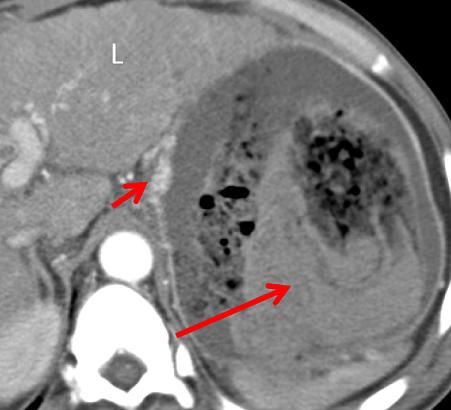

中年男性,突发恶心、呕吐。CT 增强门脉期示胃体部胃壁稍增厚,增厚的胃壁内可见散在气体,另外肠系膜静脉积气。

老年男性,气肿性胃炎,上腹部疼痛。CT 平扫示胃壁积气,腹腔及门静脉积气。